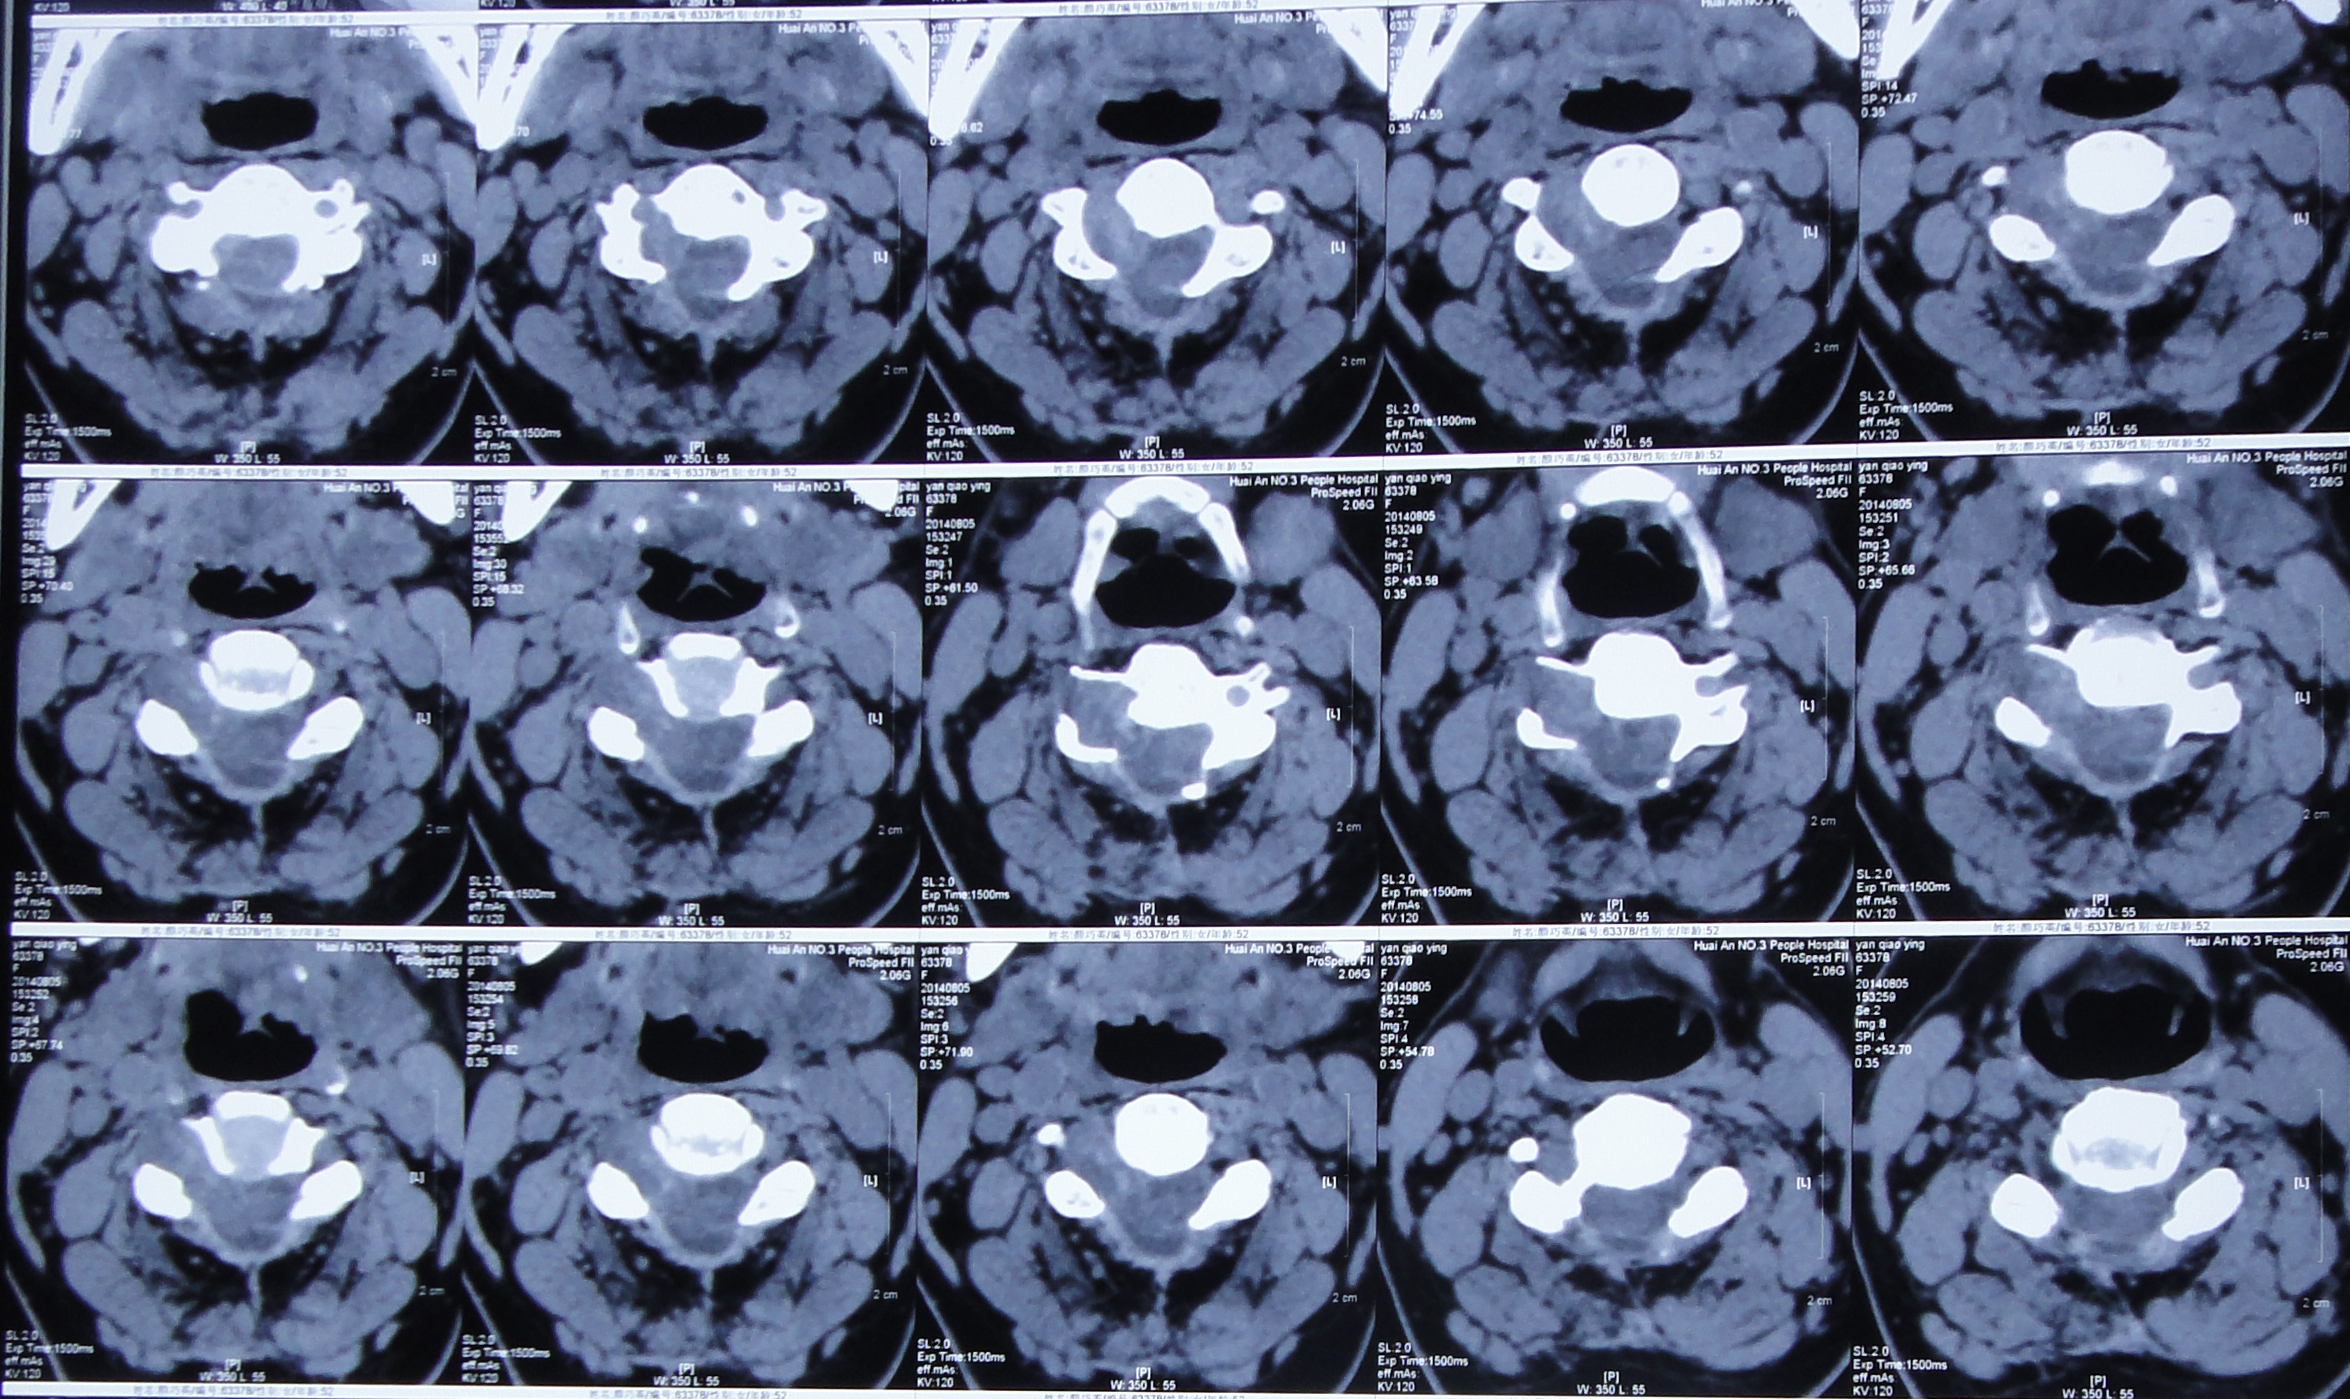

颈部神经鞘瘤影像诊断